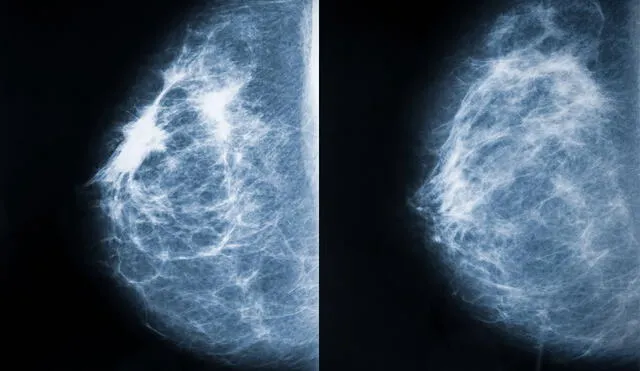

El siglo XX marcó un cambio significativo en la forma de tratar el cáncer de mama. A medida que la medicina progresaba, se desarrollaron nuevos enfoques, como la radioterapia y la quimioterapia, que complementaban las opciones quirúrgicas. Durante los años 70, los médicos comenzaron a realizar cirugías más conservadoras, como la mastectomía parcial o lumpectomía, donde solo se eliminaba una parte del tejido mamario afectado. Además, la introducción de la mamografía como herramienta de detección temprana ayudó a reducir las tasas de mortalidad, ya que permitía identificar la enfermedad en etapas iniciales.